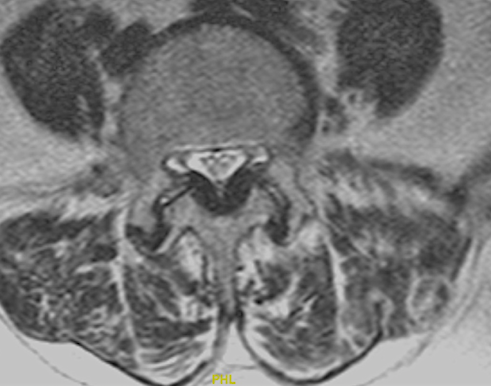

A continuación expongo imágenes de un caso prototipo donde podría estar indicado como alternativa a una descompresión y fusión larga.